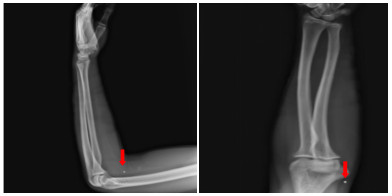

患者入院后无胸闷气促等不适主诉。入科查体:体温36.5 ℃,脉搏86次/min,呼吸频率16次/min,血压106/54 mmHg(1 mmHg=0.133 kPa),指尖氧饱和度99%~100%(未吸氧情况下),神清,瞳孔等大等圆,对光反射可,双肺呼吸音清,无明显干湿啰音,听诊心脏,律齐,无病理性杂音,左侧前臂近端及远端各一创面包扎,敷料干燥,未见明显渗出,左上肢肌力无法配合(考虑臂丛阻滞麻醉未完全恢复),余四肢肌力肌张力感觉无明显异常。立即完善相关检查(图 3、4),通过X线以及CT定位异物,超声评估异物在心脏中的活动情况及与心脏搏动时与瓣膜以及周围组织结构关系,可见异物在心脏内较固定,未影响瓣膜运动。同时血化验(动脉血气、感染指标、心肌酶谱、肌钙蛋白、D二聚体等)及心电图未见明显异常,请心胸外科会诊后建议暂予以抗炎保守对症处理。

| 图 4 外伤后第三次评估异物情况心脏超声检查图像 |

第二天,患者转入心胸外科病房继续抗炎监测,患者住院期间生命体征平稳,无不适主诉,复查相关检查检验未见明显异常且异物无明显移位,1周后出院。出院后予以患者随访至今,患者随访期间无不适主诉(如发热、心悸、胸闷等),心脏超声下见异物位置较固定,无明显移位,对心脏的正常活动无影响。